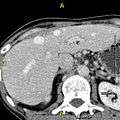

-

Axial CT image showing anomalous hepatic veins coursing on the subcapsular anterior surface of the liver.[1]